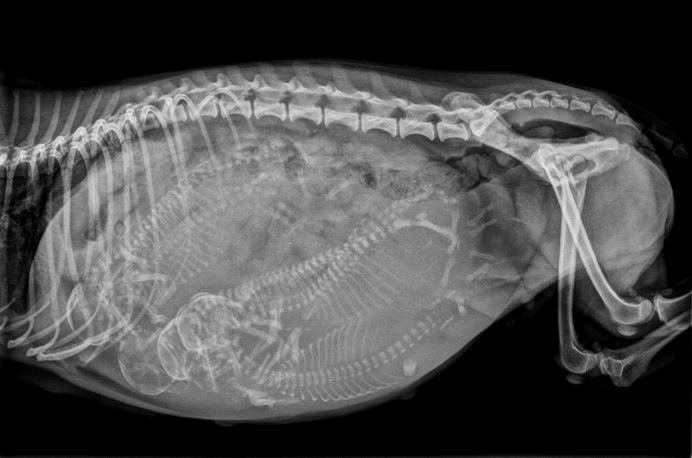

当家长们明白了或我怀疑狗狗怀宝宝后,需要明白了几个基本的数字:62天:狗狗的妊娠期一般在62天500左右15天:怀孕了后15~20天狗狗可能出现乳头涨大起来25天:如果是活虫怀孕了,也可以在第25天腹部超声判断是否怀孕40天:怀宝宝40天后狗狗腹部会膨大移位45天:怀孕了第45天也可以实际X光判断子宫里小汪的数量55天:怀孕了55天以后可以不通过X光片正式可以确定是否需要能剖产现在有狗狗有带验孕试纸,但检验结果很可能受假孕现象影响。一般来说,刚怀孕初始的3~4周内,外部仔细的观察没法可以确定狗狗是否成功受孕成功。